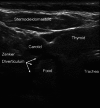

Results: Ultrasonography can be utilised to predict airway difficulty during induction of anaesthesia, evaluate if the stomach is empty or possesses gastric content that poses an aspiration risk, localise the essential cricothyroid membrane prior to difficult airway management, perform nerve blocks for awake intubation, confirm tracheal or oesophageal intubation and facilitate localisation of tracheal rings for tracheostomy. Ultrasonography is an excellent diagnostic tool in intraoperative and emergency diagnosis of pneumothorax. It also enables diagnosis and treatment of interstitial syndrome, lung consolidation, atelectasis, pleural effusion and differentiates causes of acute breathlessness during pregnancy. Patient safety can be enhanced by performing procedures under ultrasound guidance, e.g. thoracocentesis, vascular line access and help guide timing of removal of chest tubes by quantification of residual pneumothorax size.

Teaching points: • Ultrasonography is becoming essential in management of the upper and lower airways. • The tracheal structures can be identified by ultrasonography, even when unidentifiable by palpation. • Ultrasonography is the primary diagnostic approach in suspicion of intraoperative pneumothorax. • Point-of-care ultrasonography of the airways has a steep learning curve. • Lung ultrasonography allows treatment of interstitial syndrome, consolidation, atelectasis and effusion.